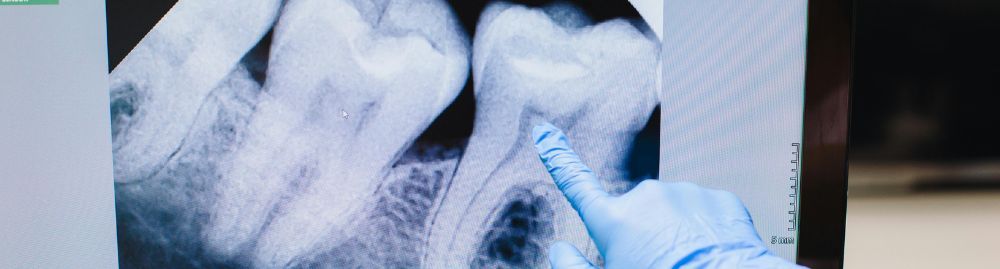

O diagnóstico do câncer de boca começa com um exame clínico detalhado feito por um cirurgião-dentista ou médico. Durante a consulta, o profissional examinará visualmente e por palpação toda a cavidade oral, incluindo lábios, bochechas, língua, gengivas e pescoço, em busca de qualquer anormalidade.

Se uma lesão suspeita for encontrada, o próximo passo é a biópsia. Nesse procedimento, um pequeno fragmento do tecido é removido e enviado para análise laboratorial (exame anatomopatológico), que confirmará ou descartará a presença de células cancerígenas.